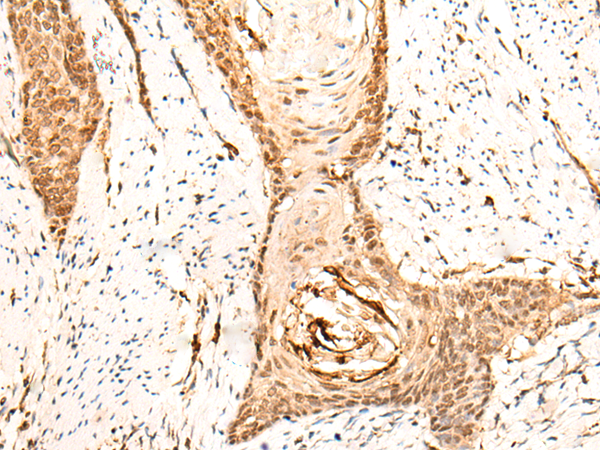

IHC positive control: |

Human lung cancer and Human esophagus cancer |

IHC Recommend dilution: |

30-150 |